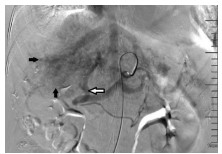

Incidence rates of hyperamylasemia and acute pancreatitis after percutaneous transhepatic biliary stenting and related risk factors

Chen XU, Wei YANG, Jie GU, Weizhong ZHOU, Haibin SHI

2021, 37(4): 882-887. DOI: 10.3969/j.issn.1001-5256.2021.04.031

Abstract(1683) HTML (492) PDF (2066KB)(66)

Abstract:

Objective  To investigate the clinical characteristics and risk factors of hyperamylasemia and acute pancreatitis after percutaneous transhepatic biliary stenting (PTBS).  Methods  A retrospective analysis was performed for the clinical data of 249 patients with malignant biliary obstruction who were admitted to Department of Interventional Radiology, The First Affiliated Hospital of Nanjing Medical University, and underwent PTBS from March 2016 to February 2020, and according to the presence or absence of postoperative hyperamylasemia or acute pancreatitis, the patients were divided into two groups to analyze incidence rate, severity, and related risk factors. The t-test or the Mann-Whitney U test was used for comparison of continuous data between groups, and the chi-square test was used for comparison of categorical data between groups. A multivariate logistic regression analysis was performed for the factors with P < 0.1 in the univariate analysis to investigate independent risk factors for hyperamylasemia and acute pancreatitis after PTBS.  Results  After PTBS, 55 patients (22.1%) patients had abnormally elevated serum amylase, among whom 26 (10.4%) were diagnosed with hyperamylasemia and 29 (11.7%) were diagnosed with acute pancreatitis. All patients with acute pancreatitis had mild manifestations. The multivariate logistic regression analysis showed that age ≤60 years (odds ratio [OR]=2.2, 95% confidence interval [CI]: 1.07-4.52, P=0.033), iodine-125 seed strand implantation (OR=2.8, 95%CI: 1.21-6.45, P=0.016), biliary stent placement across the papilla (OR=6.3, 95%CI: 2.85-14.05, P < 0.001), and visualization of the pancreatic duct during surgery (OR=13.9, 95%CI: 5.64-34.03, P < 0.001) were risk factors for hyperamylasemia and acute pancreatitis after PTBS.  Conclusion  Hyperamylasemia and acute pancreatitis are relatively common complications after PTBS. Age ≤60 years, iodine-125 seed strand implantation, biliary stent placement across the papilla, and visualization of the pancreatic duct during surgery are independence risk factors for hyperamylasemia and acute pancreatitis after PTBS.